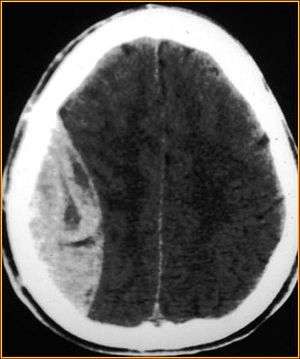

Epidural hematoma. Note the biconvex shape hemorrhage.

On images produced by CT scans and MRIs, epidural hematomas usually appear convex in shape because their expansion stops at the skull's sutures, where the dura mater is tightly attached to the skull. Thus they expand inward toward the brain rather than along the inside of the skull, as occurs in subdural hematoma. The lens-like shape of the hematoma causes the appearance of these bleeds to be "lentiform."